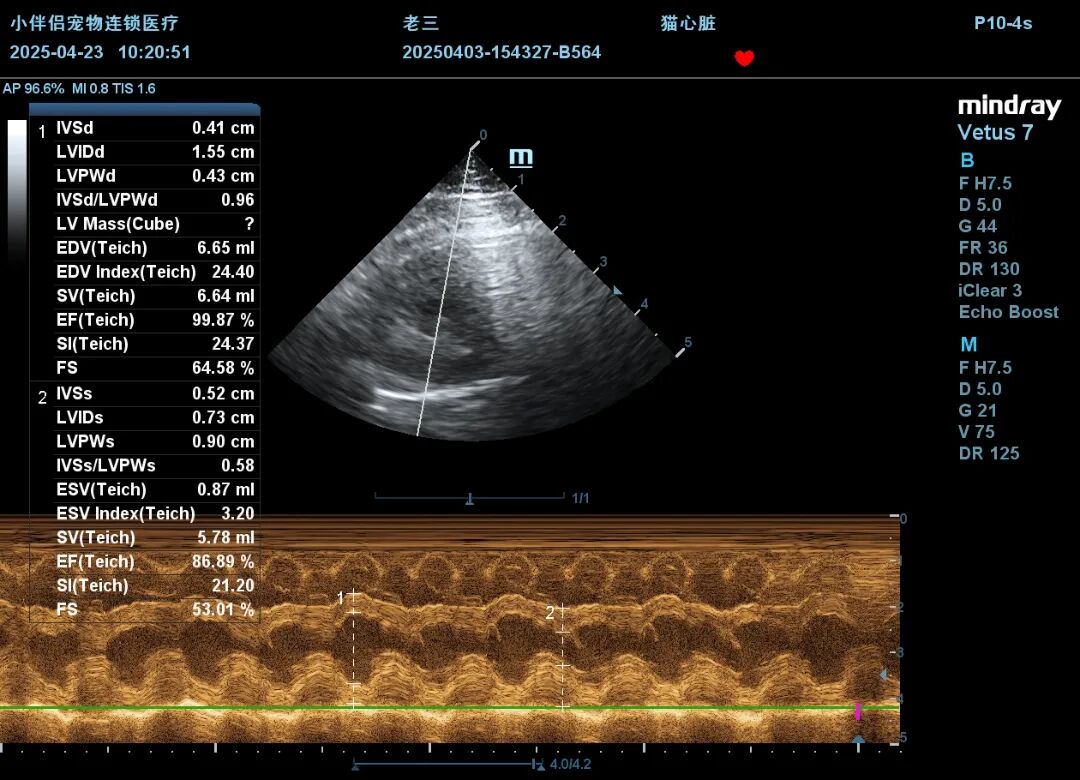

之后,针对症状进行利尿、吸氧等治疗措施,并进行每日心超复查。经过治疗后,猫咪状态逐渐好转,于肺水肿发病后第七天出院。出院半个月后,进行二次复查,心超及 BNP 指标均已恢复正常。二次复查的心超结果如下:

4.23心超M超.JPG

该病例最终被诊断为自发性膀胱炎及猫短暂性心肌增厚(TMT)